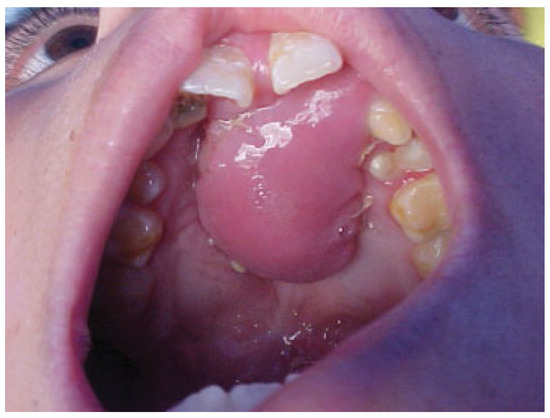

Case 11

An 8-year-old boy with a history of bilateral cleft lip and palate presented with an anterior fistula measuring 33 × 19 mm after palatal surgery (Figure 9). The fistula was closed with a left anteriorly based NAMMC flap (Figure 10).

Figure 9. Severe fistula located on the hard palate after primary palatoplasty in an 8-year-old patient with bilateral cleft lip and palate.

Figure 10. Postoperative (2 weeks) view of the patient in Figure 9 after closure of the fistula using an anteriorly based nasal artery musculomucosal cutaneous flap.